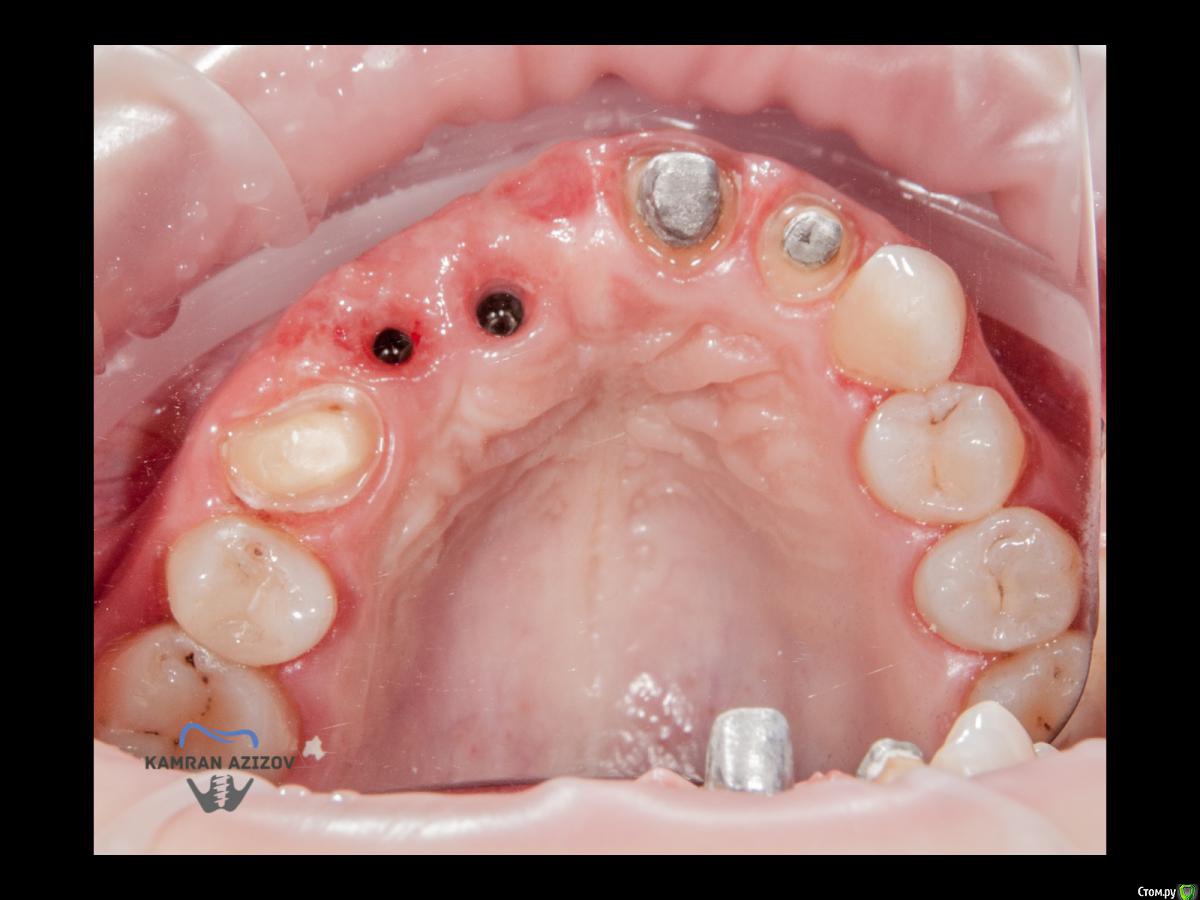

kamranchick Опубликовано 11 апреля, 2019 Автор Поделиться Опубликовано 11 апреля, 2019 Рекол 6 месяцев Ссылка на комментарий